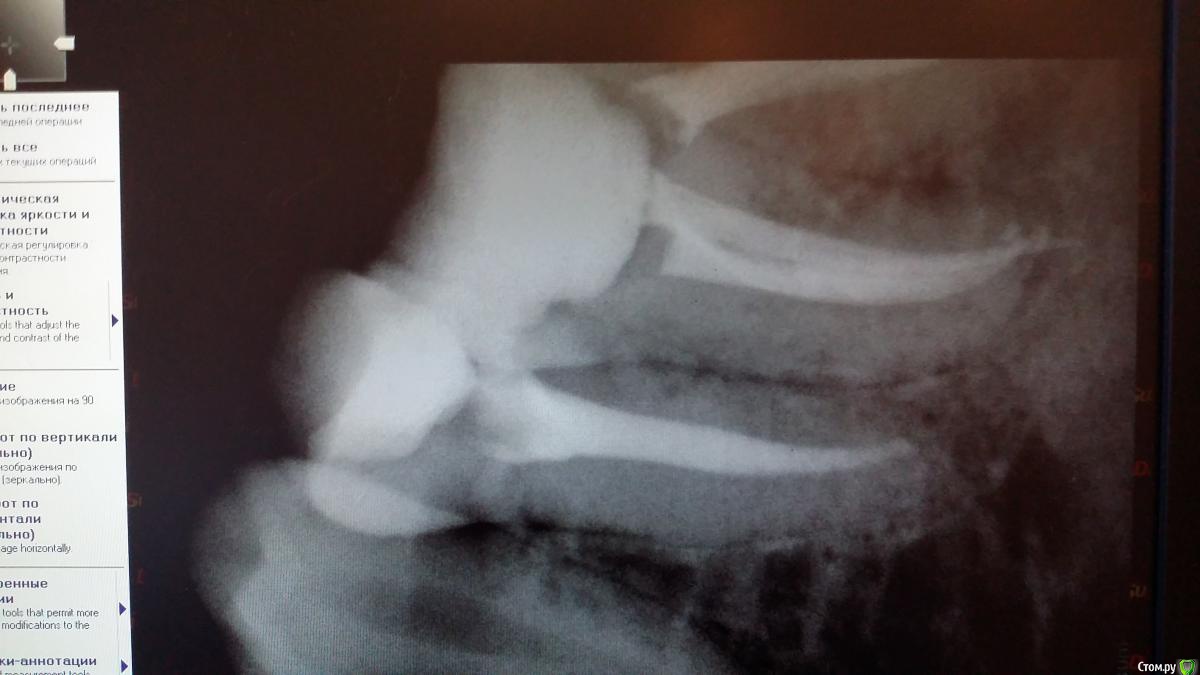

Recive Опубликовано 9 февраля, 2015 Поделиться Опубликовано 9 февраля, 2015 Жалобы: классический пульпит./периодонтитанамнез:эндэндодонтия первичнаялечение:ммо кк первое посещение пульперил, да не будет больеть! Аминь)Второе- в мщ, мя каласепт в дистальном метапаста (ннагнитал каналонаполнителем в надежде найти дельту в апексе)Третье - через неделю замена каласепта на каласепт, и в дистальный крезофен, для надежности.Четвертое на 16.02 пломбировать если не будеет болеть. Ваше мнение и варианты .первый снимок при поступлениивторой при прохождениивторой контроль метапасты и каласепта1.02. 09.02. 1 1 Ссылка на комментарий

Чертков Александр Опубликовано 11 февраля, 2015 Поделиться Опубликовано 11 февраля, 2015 Оценивая динамику рентгенограмм посмею предположить что Вы там создали пробку из опилок - поскольку на рентгенограмме с инструментом Вы у апекса, а на следующей уже "недолёт"...отмывайте нормально канал (нет УЗ- активируйте инструментом) и пакуйте. Коронка - обязательно! 1 Ссылка на комментарий

Recive Опубликовано 11 февраля, 2015 Автор Поделиться Опубликовано 11 февраля, 2015 Оценивая динамику рентгенограмм посмею предположить что Вы там создали пробку из опилок - поскольку на рентгенограмме с инструментом Вы у апекса, а на следующей уже "недолёт"...отмывайте нормально канал (нет УЗ- активируйте инструментом) и пакуйте. Коронка - обязательно! Хм....мыл на 2м посещении очень много(минут 5 один канал), дабы отмыть метапасту.там 08 ример стучит как в пробку... Ссылка на комментарий

Catherine Опубликовано 11 февраля, 2015 Поделиться Опубликовано 11 февраля, 2015 Может быть, это последствия трудного трудового дня, но мне на первом снимке в дистальном отделе вообще две верхушки видятся... Ссылка на комментарий